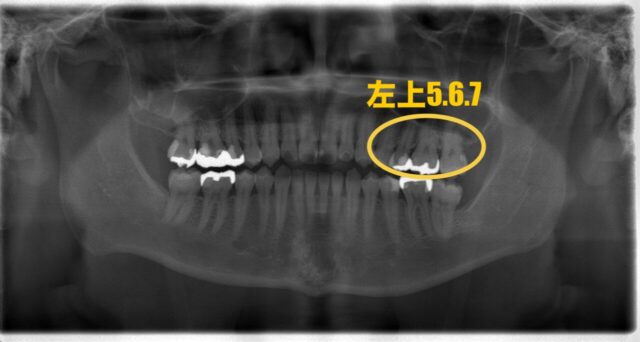

今回の部位は左上5、6、7です。

5番目と6番目にはメタルインレー、7番目にはCR(レジン)が詰められています。

こちらはレントゲン写真です。

痛みがあるのは6番目の歯ですが前後の歯にも感染が見られたため、一緒に治療することになりました。